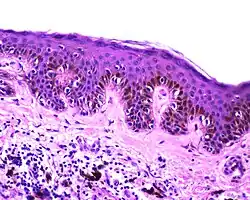

| Dysplastic nevus | Usually a compound nevus with cellular and architectural dysplasia. Like typical moles, dysplastic nevi can be flat or raised. While they vary in size, dysplastic nevi are typically larger than normal moles and tend to have irregular borders and irregular coloration. Hence, they resemble melanoma, appear worrisome, and are often removed to clarify the diagnosis. Dysplastic nevi are markers of risk when they are numerous, such as in people with dysplastic nevus syndrome. According to the National Institute of Health (NIH), doctors believe that, when part of a series or syndrome of multiple moles, dysplastic nevi are more likely than ordinary moles to develop into the most virulent type of skin cancer called melanoma.[20] | ![]() In this case, the central portion is a complex papule, and the periphery is macular, irregular, indistinct and slightly pink. |

Characteristic rete ridge bridging, shouldering, and lamellar fibrosis. H&E stain.